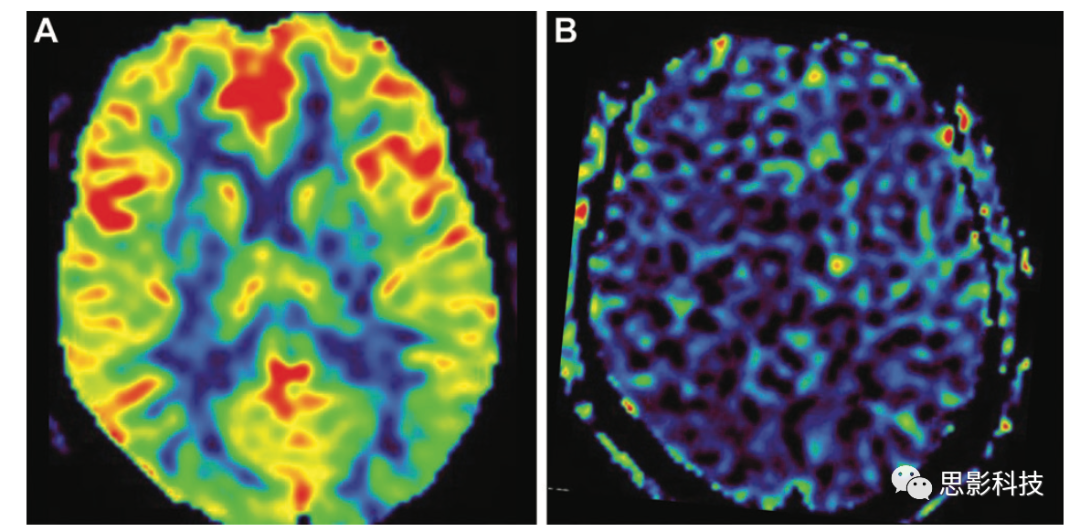

ASL圖正常血流灌注顯示皮質(zhì)、基底節(jié)和丘腦灰質(zhì)信號(hào)強(qiáng)度增強(qiáng)(黃色、橙色和紅色)(A),以及白質(zhì)信號(hào)強(qiáng)度降低(藍(lán)色)。注射Gd造影劑后的ASL(B)顯示整個(gè)大腦完全沒有信號(hào),代表自旋標(biāo)記偽影的丟失。